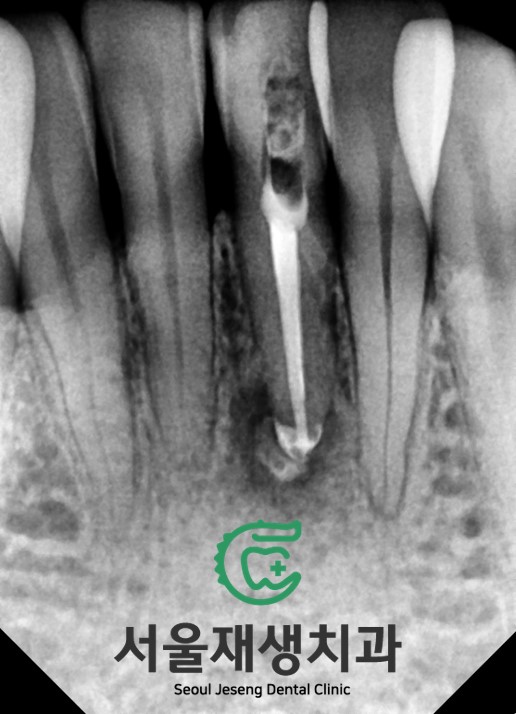

신경치료를 먼저 시행해줍니다.

![[치아미백] 예전에 부딪힌 앞니가 까맣게 변했어요. 신경이 죽은 치아를 하얗게 돌려놓기! (서울재생치과) 관련 이미지 6](https://pub-9f2bb3498faf4d1d8714b41df24753e3.r2.dev/content/clinics/archive/nqmm0udu86/naver_blog/honeybeevuvu/assets/by_hash/664d8bf8646daf1cf433dfa0e763677509ff56396f15e0b979f34ef27d097aec.jpg)

뿌리 내에 있는 오염된 조직들을 제거하고,

깨끗하게 밀봉해주었습니다.

이제 미백을 시작할 차례!

![[치아미백] 예전에 부딪힌 앞니가 까맣게 변했어요. 신경이 죽은 치아를 하얗게 돌려놓기! (서울재생치과) 관련 이미지 7](https://pub-9f2bb3498faf4d1d8714b41df24753e3.r2.dev/content/clinics/archive/nqmm0udu86/naver_blog/honeybeevuvu/assets/by_hash/0f4f80ba89b1b2e40b41b285c49582d213210b0d86a877aca7cec285e797b805.jpg)

신경치료 약제 위로

뿌리를 보호하는 바닥재를 도포한 후,

변색이 일어난 머리 부위에

미백제를 채워줍니다.

임시충전재로 구멍을 매꿔주면 끝!

일주일 간격으로 두 세 번 미백제를

교체해주면 곧 하얀 치아로 돌아옵니다.

신경치료 후 시행하는 미백치료는

효과가 빠르고 오랜기간 안정적으로

유지된다는 특징이 있습니다^^